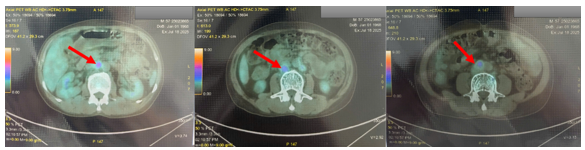

Chụp cắt lớp phát xạ positron PET/CT:

1. Hình ảnh vài hạch thượng đòn trái (SUVmax: 2.85), nhiều hạch ổ bụng (SUVmax: 4.89), hạch chậu hai bên (SUVmax: 4.66) tăng chuyển hóa FDG tương ứng với hạch ác tính. Đối chiếu với mô bệnh học, hóa mô miễn dịch.

2. Hình ảnh tổn thương khuyết xương ở thân đốt sống L4, xương chậu phải, xương mu phải, tăng chuyển hóa FDG khả năng ác tính (SUVmax: 3.08).

3. Hình ảnh tăng chuyển hóa FDG ở amidam bên phải (SUVmax: 3.71) Đối chiếu với nội soi.

4. Hình ảnh nốt giảm tỷ trọng ở nhu mô gan hạ phân thùy IV, tăng nhẹ chuyển hóa FDG (SUVmax: 2.76). Cần phối hợp đánh giá thêm.

5. Hình ảnh vài nốt mờ dưới màng phổi và sát rãnh liên thùy ở thùy dưới phổi phải và thùy trên phổi trái, không tăng chuyển hóa FDG. Nên lưu ý bệnh lý viêm. (Đối chiếu với CT scanner lồng ngực: phù hợp với hình ảnh)

Hình 1. Hình ảnh PET/CT toàn thân của bệnh nhân.

Hình 3. Hình ảnh nhiều hạch ổ bụng (SUVmax: 4.89) tăng chuyển hóa FDG tương ứng với hạch ác tính (mũi tên đỏ). Đối chiếu với mô bệnh học, hóa mô miễn dịch.

Kết quả PET/CT toàn thân của bệnh nhân tuy không phát hiện được tổn thương nguyên phát, nhưng phát hiện được rất nhiều các tổn thương di căn hạch trong ổ bụng-tiểu khung như nhiều hạch cạnh động mạch chủ, hạch dọc bó mạch chậu 2 bênvới kích thước lớn và SUVmax cao, ngoài ra còn có xương đốt sống, cánh chậu, và gan. Với những thông tin có được từ PET/CT, bác sĩ lâm sàng có thể lựa chọn các vị trí khác nhau để sinh thiết lại tổn thương tìm nguồn gốc u (ví dụ: xương,gan). Đồng thời cũng đặt ra cân nhắc về nội soi tai mũi họng lần thứ hai để khẳng định lại tính chất của tổn thương amidan phải phát hiện trên PET/CT nhưng chưa nhìn được trong nội soi tai mũi họng lần đầu tiên.